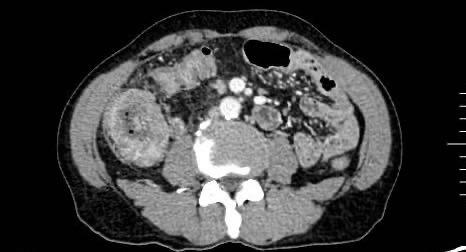

图1 CT检查提示升结肠管壁不均匀增厚,伴区域内多发肿大淋巴结Fig.1 Abdominal CT showing irregular thickening of the ascending colon wall with multiple enlarged regional lymph nodes